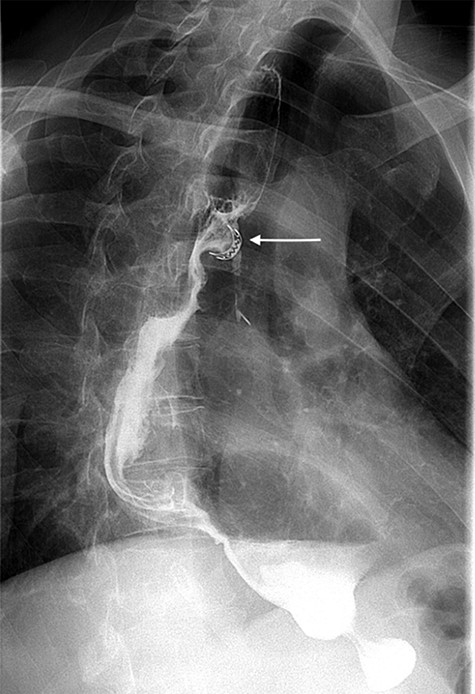

A 49-year-old male, with past medical history of tobacco smoking, who was diagnosed with adenocarcinoma of gastroesophageal junction underwent minimally invasive two-stage oesophagectomy. A month following discharge, he presented with complains of chest pain and persistent coughing (Ohno’s sign); barium swallow examination was conducted. This demonstrated a gastrobronchial fistula, between the newly formed gastric conduit and the left main bronchus (Figures 1 and 2). On endoscopic evaluation, a 5 mm communication between the tip of the gastric conduit and the left main bronchus with no evidence of ischemia and well-vascularised edges was noted.

Lateral view of barium swallow demonstrating gastrobronchial fistula.